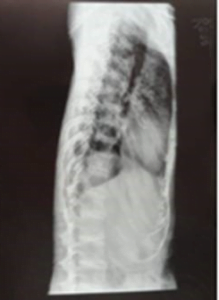

The patient has lateral thoracolumbar spine with intervertebral disc calcification (Fig. 2)

Fig. 2: Lateral thoracolumbar spine with intervertebral disc calcification

While DISH can cause ligamentous ossification, the involvement of intervertebral discs is not a characteristic feature. The patient's lateral thoracolumbar spine with intervertebral disc calcification is more suggestive of other conditions.

Characteristic radiological findings in alkaptonuria include vertebral disc calcification, chondrocalcinosis, and osteoarthritis of multiple joints, especially the spine. These findings contribute to the clinical manifestations of premature degenerative arthritis in affected individuals.